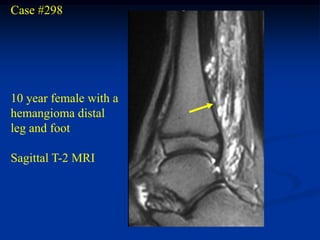

Case #298

10 year female with a

hemangioma distal

leg and foot

Sagittal T-2 MRI

Axial T-2 MRI

Sagittal T-1 MRI foot

Case #298 10 yearfemale with a hemangioma distal leg and foot Sagittal T-2 MRI

• 314.

• 315.

• 316.

• 317.

• 318.